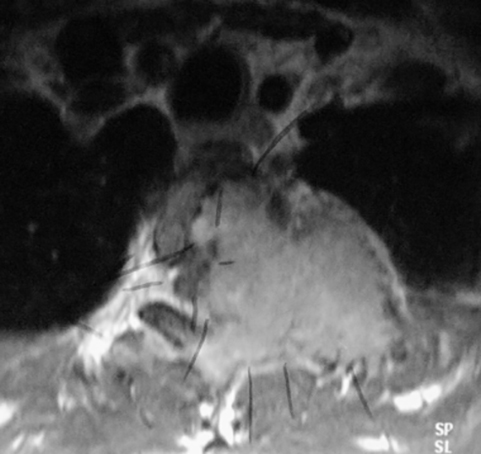

Infección

Las causas infecciosas se deben considerar en la evaluación de un niño con dolor de espalda. La discitis aparecen en dos picos de edad, en niños menores de 5 años y en niños de 10 a 14 años (36). La presentación puede ser tan variada que puede incluir además de dolor de espalda, dolor abdominal, cojera o rechazo al caminar. El examen físico mostrará límite al movimiento de la espalda y dolor a la palpación localizada. Radiográficamente los hallazgos se observan atrasados con relación a los hallazgos físicos. De verse algún hallazgo, será la irregularidad de los bordes vertebrales, usualmente entre L2-L3 o L3-L4. El mejor estudio es la cintigrafía ósea para localizar la lesión y la RM para definir la extensión especialmente si hay un absceso epidural, que requiera drenaje quirúrgico inmediato (Figura 5). Los laboratorios mostrarán una elevación de la velocidad de sedimentación, mientras que el nivel de glóbulos blancos solo se elevará en un 10% - 40% de los casos. Por lo tanto, el nivel de los glóbulos blancos no es confiable (36).

El tratamiento debe ser descanso, abrazadera para inmovilizar la columna vertebral y antibióticos intravenosos. Empíricamente el antibiótico debe ser encaminado a cubrir se estafilococo aureus, que es el organismo más común. El tratamiento quirúrgico se reserva a los casos en que el paciente no mejore en varios días con el descanso y antibióticos o cuando se ha documentado la presencia de un absceso epidural (37).Osteomielitis vertebral